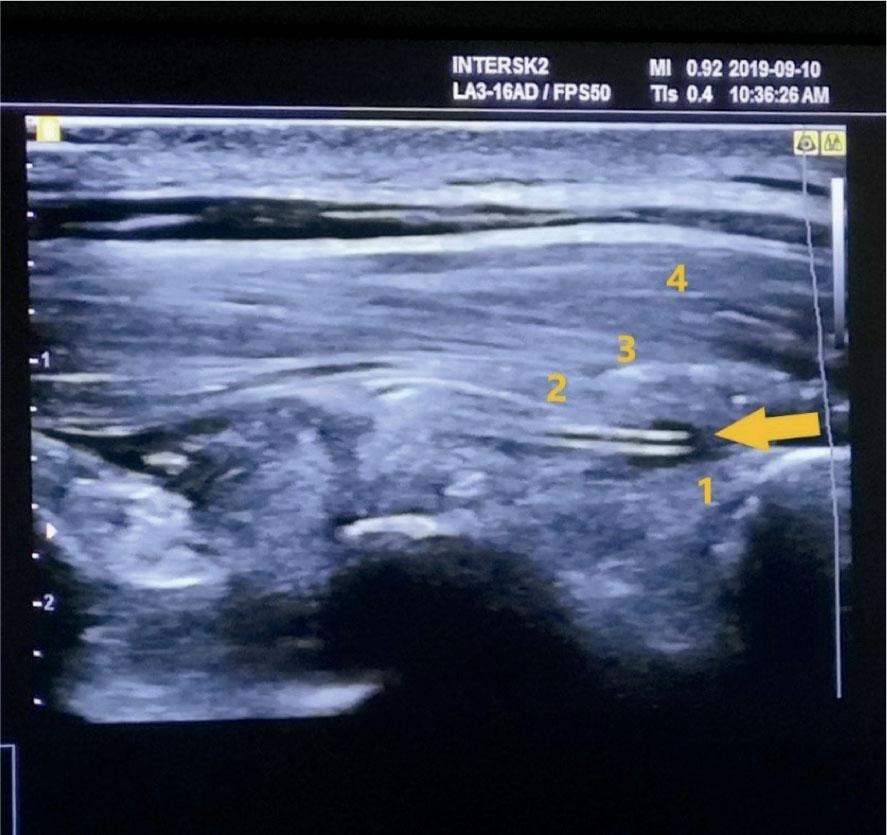

Two anesthesiologists, experienced in regional anesthesia, were inserting catheters to the patients before the surgery in the pre-op area. The standard monitoring and i.v. canal were applied before the intervention. The ESPB catheter insertion was performed using Samsung© ultrasound with a GE 12L-RS high-frequency linear probe. Aseptic conditions were guaranteed by using sterile drapes, sterile probe dressings, gloves, masks, and surgical gowns. The catheter insertion underwent in a pronated position with the patient lightly sedated by 1–2 mcg/kg fentanyl. The insertion site was infiltrated with 2 ml of 2% lidocaine on the T4 level of the spine, approximately 3 cm ipsilateral from the midline on the transverse process. The needle was then inserted under ultrasound guidance, positioning the needle tip immediately above the periosteum. The position was confirmed by injecting approximately 10 ml of 0.9% sodium chloride solution, which caused a hydro-dissection between the erector spinae muscle and the underlying fascia. Then, the catheter was inserted 4–6 cm above the needle tip. (Figure 1). After needle extraction, the catheter was secured using Stat-Lock© and multiple see-through coverings (Tegaderm©). Anesthesiologists used an 18G, 80 mm BD Microlance© pointed needle and a 20G Braun© multi-orifice epidural catheter.

Ultrasound image of the inserted ESPB catheter (marked by an arrow) and interfascial hydro-dissection.

1 – underlying thoracic lamina, 2 – m. erector spinae, 3 – m. rhomboideus, 4 – m. trapezius